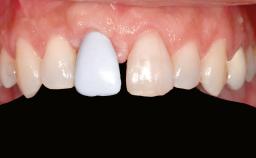

Ridge Preservation and Implant Placement for a Fixed Dental Prosthesis After a Car Accident

It is well known to clinicians that any removal of teeth will, over time, cause the dimensions of the alveolar ridge to be reduced by resorption of the bundle bone and by changes related to external modeling. This development is particularly evident in the crestal region with its thin buccal bone that consists of bundle bone almost entirely. The facial bone will rapidly resorb as blood supply from the periodontal ligament gets disrupted (Araújo and Lindhe 2005). There is no reason why traumatic tooth loss should not have the same consequences. It takes more than achieving implant osseointegration for a treatment outcome to be considered successful. No deficiency of bone or soft tissue is acceptable when an ideal esthetic outcome is the goal. Several articles (Sanz and coworkers 2011; Vignoletti and coworkers 2011) have reported on techniques of improving the alveolar ridge for implant treatment, notably focusing on protecting tissues from resorption.

Soft Tissue Anatomy Intact Defective

Bone Volume Horizontally and vertically sufficient Horizontally deficient Deficient vertically or deficient vertically AND horizontally